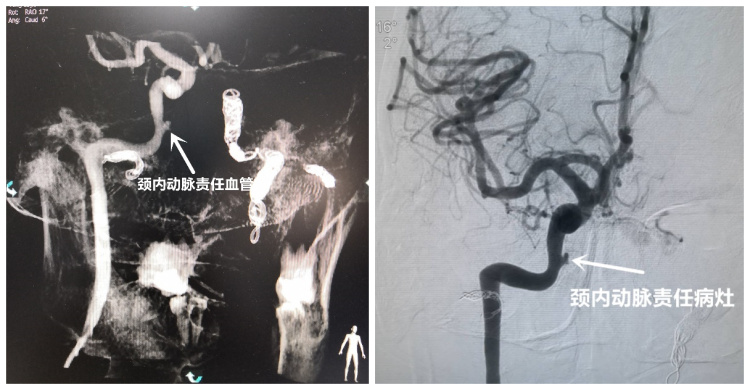

耳鼻咽喉科联合介入科成功抢救一名颈内动脉破裂大出血患者